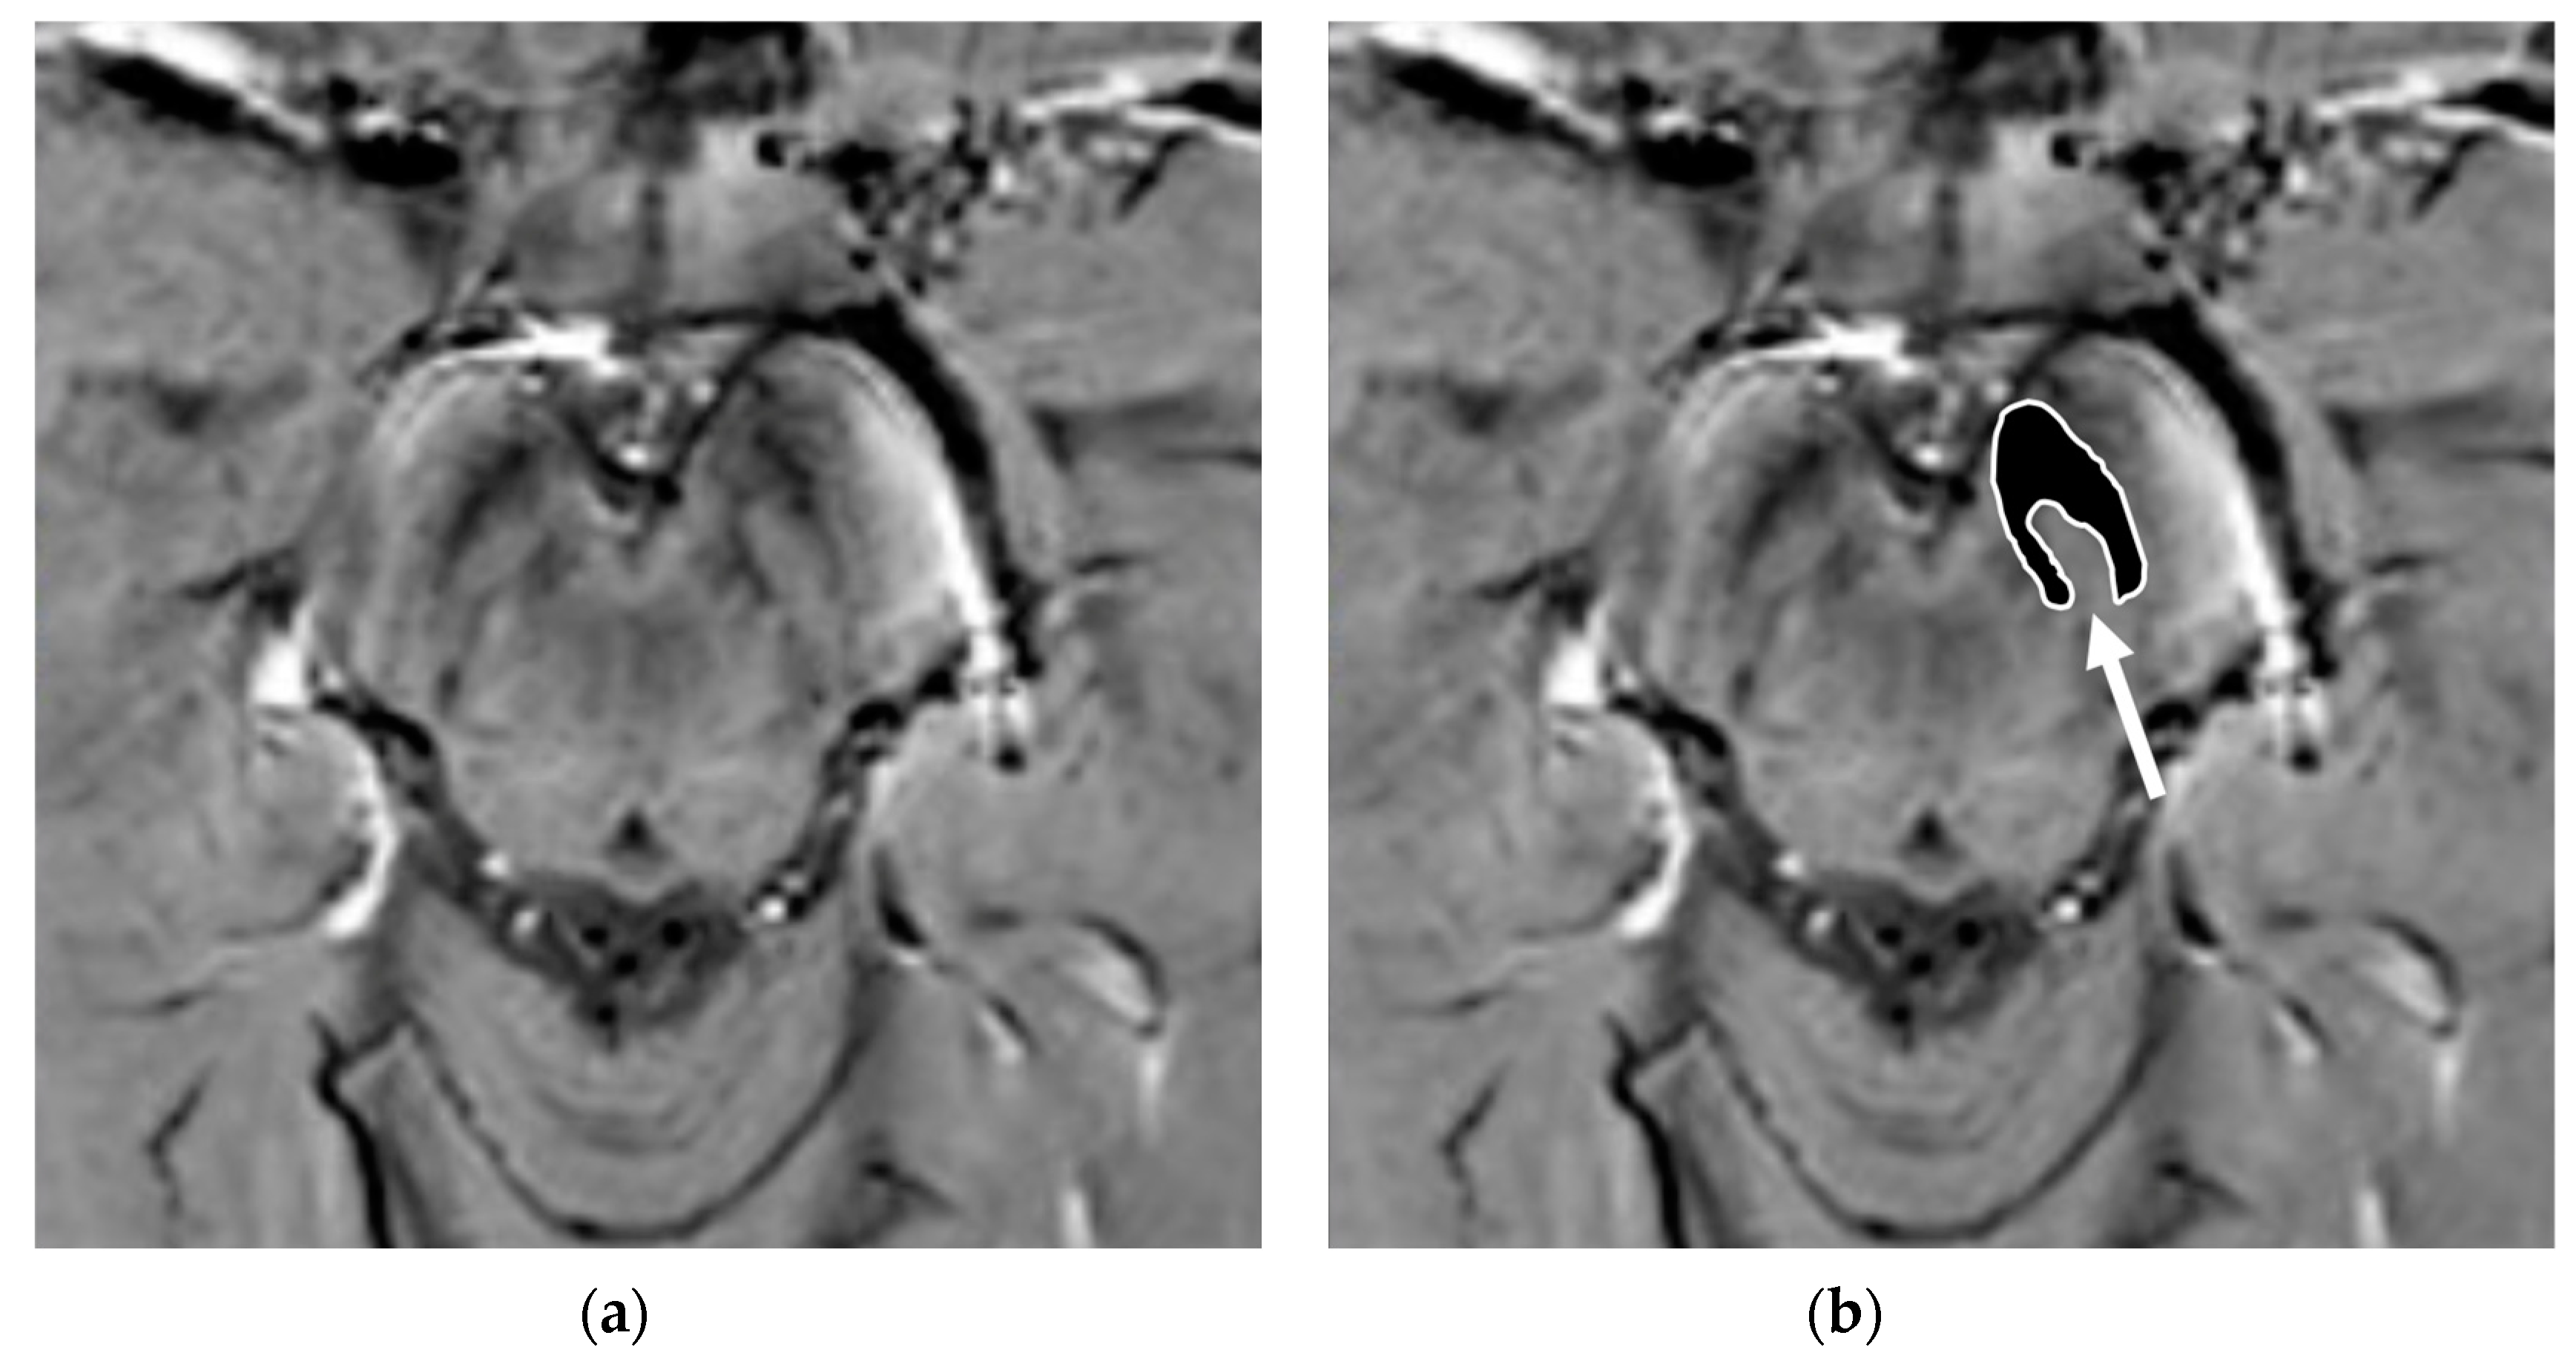

Nigrosomes are dopaminergic neurons within the SNc that are characterized by high NM levels and a paucity of iron. They can be subdivided into five different regions (nigrosome 1 to 5), the largest of which, nigrosome-1 (located in the dorsolateral part of SNc [12]), has been shown to play a key role in the neuropathology of PD. Indeed, the greatest loss of dopaminergic neurons in PD patients occurs in the nigrosome-1. It was first detected in vivo by 7.0-Tesla (7T) MRI as a hyperintense, ovoid area on T2*-weighted images, within the dorsolateral border of the hypointense SN pars compacta [37,38]. Similar findings can be found with the more commonly used 3-Tesla (3T) MRI [39]. By using T2* or susceptibility-weighted imaging (SWI), researchers have also termed this region dorsolateral nigral hyperintensity or a swallow-tail sign (STS) (Figure 3).

Figure 3.

Susceptibility-weighted imaging (SWI) scan performed with a 3T MR scanner in a normally aging brain of a 65-year-old male who underwent a brain MRI examination for persistent headaches. A raw slice passing through the mesencephalon (a) and the same slice with superimposed highlighted SNc (white surrounded black ROI), thereby demonstrating the normal appearance of the nigrosome-1 (hyperintense area pointed by the white arrow) or swallow-tail sign (b).

Normal nigrosome-1 and the surrounding structure of the dorsolateral SN appear as a swallow tail [40], and they can be visualized in 95% of healthy subjects [41,42]. Iron deposits and microvessels have been reported as contributing to the hyposignal surrounding nigrosome-1 in the SWI of normal aged midbrains [43]. Nigrosome-1 in PD patients displays a significant loss of STS on T2* weighted images, probably due to a reduction in NM within dopaminergic neurons, an increase in free iron (which induces local inhomogeneity in the magnetic field resulting in signal loss), or a loss of paramagnetic NM–iron complexes [44,45]. As the disease advances, a loss of T2* hyperintensity in PD has been demonstrated to progress from nigrosome-1 to nigrosome-4 [46]. The absence of STS may assist in the differential diagnosis for PD if compared with controls and ET, ultimately reaching high sensitivity and specificity [17,40,47,48] (Figure 4).